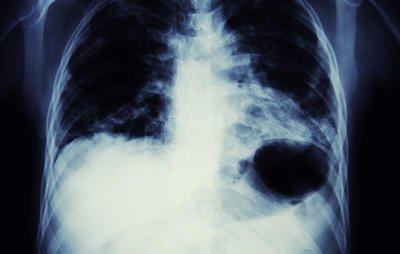

On Friday, UNC School of Medicine researchers released a study showing a direct link between e-cigs and certain lung diseases. The researchers found that e-cigs cause a “significant” increases in neutrophils, which can contribute to inflammatory lung diseases, such as COPD and cystic fibrosis.

As Harvard Health Publishing reported, many e-cigs contain a chemical compound called diacetyl, which is associated with a rare lung disease called bronchiolitis obliterans. According to the National Institutes of Health, those with bronchiolitis obliterans have damaged and inflamed bronchioles, which are the lung’s tiniest airways.